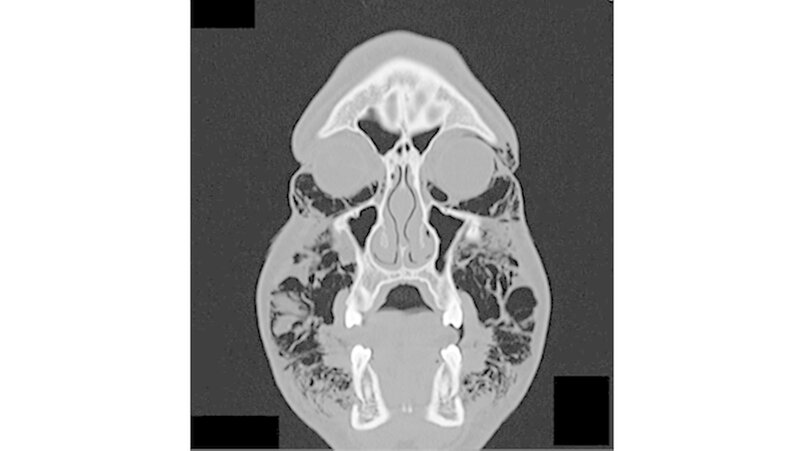

Permanent wiederholte er das Valsalva-Manöver, indem er Atemluft gegen seine verschlossenen Lippen presste. Bei der Aufnahme war der Patient hämodynamisch stabil. Die Funktionen von Nervus facialis sowie Nervus trigeminius waren normal. Auch die Entzündungswerte befanden sich im normalen Bereich. Klinisch war eine umfangreiche Schwellung im gesamten Gesichtsbereich sichtbar. Zudem hatte der Patient Schwierigkeiten, die Augen zu öffnen (Abbildungen 1 und 2).

Bei der Palpation war eine offensichtliche Schwellung der Periorbitalregion, der Wangen sowie der Supraklavikulargruben tastbar. Der enorale Befund zeigte eine nicht vollständig geschlossene Extraktionsalveole. Eine Entzündung war jedoch nicht zu erkennen. Mundboden und Rachenbereich waren von der Luftansammlung nicht betroffen. Der Patient konnte schlucken, doch das Atmen fiel im schwer.